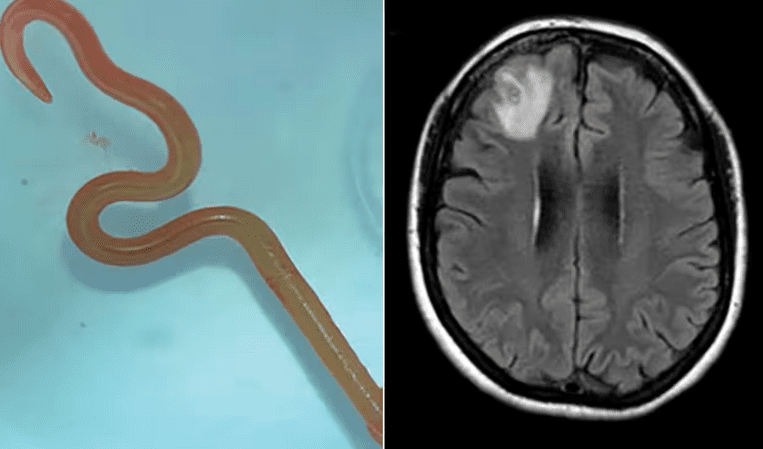

Ένα ζωντανό σκουλήκι, μήκους οκτώ εκατοστών, αφαιρέθηκε χειρουργικά ζωντανό από τον εγκέφαλο μιας 64χρονης γυναίκας στην Αυστραλία.

Όπως γράφει η Australian Guardian, η 64χρονη είχε παραπονεθεί για πόνους στο κεφάλι και προβλήματα μνήμης. Ανέλαβαν οι νευροχειρουργοί σε νοσοκομείο της Καμπέρα για να την εξετάσουν. Αρχικά υπέθεσαν ότι η αιτία ήταν ένας «τραυματισμός». Κατά τη διάρκεια της επέμβασης, ωστόσο, βρήκαν και αφαίρεσαν ένα ζωντανό σκουλήκι. Το παράσιτο ήταν Ophidascaris robertsi, το οποίο συνήθως απαντάται μόνο σε πύθωνες, σύμφωνα με μελέτη που δημοσιεύεται στο περιοδικό Emerging Infectius Diseases.

. Στη συνέχεια η γυναίκα μεταφέρθηκε στο νοσοκομείο της Καμπέρα. Μια μαγνητική τομογραφία του εγκεφάλου της αποκάλυψε τελικά ανωμαλίες που απαιτούσαν χειρουργική επέμβαση.